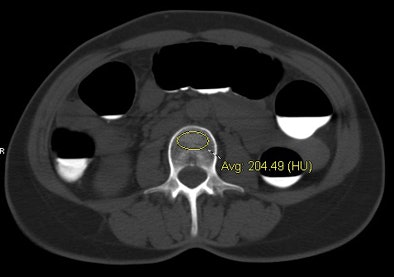

| CT data from virtual colonoscopy exam shows individual with normal BMD (top) and another with osteoporosis (bottom). Both cases were assessed at the L3 level using the simple ROI method, with results confirmed by DEXA. Images courtesy of Perry Pickhardt, MD. |

"We simply lay an ovoid ROI and measure the mean attenuation in Hounsfield units," he said. Reconstructions were performed at both 1.5-mm and 5-mm thicknesses and the two were compared -- but the focus was on 5-mm thicknesses because they are compatible with any routine CT study.

For example, at the L3 level, a trabecular attenuation threshold of 130 HU was 100% sensitive for osteoporosis (29/29); 61 (72.6%) of 84 adults with normal BMD were above the 130 HU threshold, while 108 (82.4%) of 131 below 130 HU had osteopenia or osteoporosis at DEXA. Similar results were found for other T12-L5 levels; complete results are shown below.